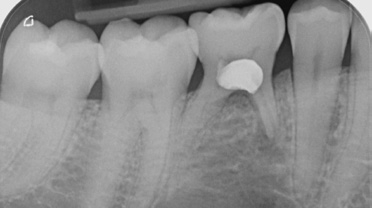

Die intraorale Röntgenaufnahme zeigte die übliche 2-wurzelige Konfiguration des Milchmolaren, apikal das Foramen mentale sowie gering ausgeprägte trabekuläre Strukturen der regionalen Spongiosa aufgrund der kurzen Wurzelkonfiguration (Abb. 2). Eine geführte Implantation, für deren Umsetzung ein DVT angefertigt wurde (Orthophos XG 3D), bot hier den Vorteil einer sicheren Führung ohne Richtungsablenkung durch die bestehenden Alveolen sowie der optimalen Ausnutzung des vorhandenen Raumangebots, um maximale Stabilität zu erreichen. Aufgrund der größeren mesiodistalen Breite des Zahnes 85 im Vergleich zu üblichen Prämolaren orientierte ich mich bei der prothetischen Planung am vorhandenen Milchmolaren.

Nach der geführten Implantatbettaufbereitung wurde das Astra Tech Implant System EV 4,8C × 13 mm durch die Hülse hindurch mit Höhenanschlag in seine geplante Position inseriert (Eindrehmoment final: 45 Ncm) (Abb. 8 bis 10). Die Lage des Implantats wurde mit einer intraoralen Röntgenaufnahme postoperativ überprüft (Abb. 11). Es folgte die digitale Abformung mit der CEREC Omnicam: Um die Implantatposition exakt zu übertragen, wurde ein Scanbody platziert (Abb. 12). Der dabei erzeugte Scan wurde für das präzise Design eines Provisoriums mit der Abformung des Milchzahnes überlagert und im Anschluss gefräst (Abb. 13). Das Kunststoffprovisorium wurde mit der dazugehörigen TiBase verklebt (Multilink Hybrid Abutment, Ivoclar Vivadent). Zuvor wurden sowohl die TiBase als auch das Zirkonabutment sandgestrahlt, im Ultraschallbad gereinigt und im Anschluss silanisiert (Monobond plus, Ivoclar Vivadent). Im nächsten Schritt wurde das Provisorium mit dem Implantat okklusal verschraubt (Abb. 14) und mit Komposit verschlossen (Abb. 15 bis 17). Um eine Überbelastung des Implantats während der Einheilzeit zu vermeiden, war eine Nonokklusion von 0,5 bis 1 mm zum Antagonisten zu beachten. Dazu gehörte auch die Empfehlung an die Patientin, das Provisorium in den ersten Monaten nur eingeschränkt zu belasten (weiche Kost).